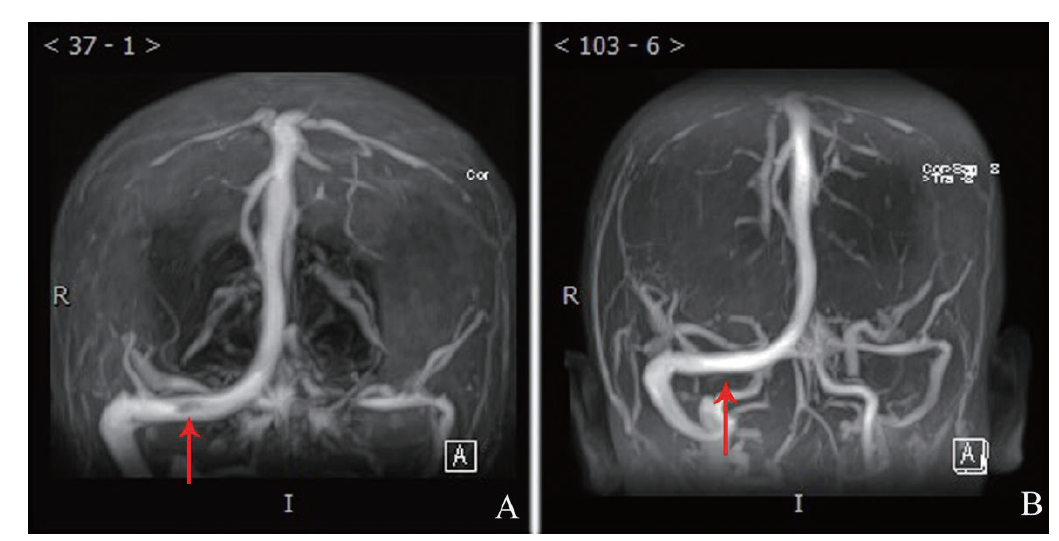

图1 一例蛋白S缺乏症合并CVST患者治疗前、后MRV

A:治疗前,红色箭头所示为血栓;B:治疗后,红色箭头示血栓消失

例1 患者女,17岁,高三在读学生。因头痛、头晕、呕吐4 d于2020年4月16日入我院。2020年4月12日患者于上课时突发头痛、头晕,伴恶心及呕吐,当时未予重视,其后症状逐渐加重,于4月16日至我院行头部CT平扫,结果提示:①左侧丘脑局部密度可疑降低,建议行MRI检查;②直窦及窦汇内高密度影,未排除血栓形成,建议进一步检查。当日立即完善头颅MRI、磁共振血管造影(MRA)和MRV,结果提示:①考虑双侧放射冠、丘脑、胼胝体压部静脉性梗死(亚急性期);②颅脑MRA检查未见明显异常;③直窦及窦汇血栓形成(图1)。收入我院神经科后体格检查示:神清语晰,对答切题,记忆力、定向力、计算力正常,查体合作。双侧瞳孔等圆等大,直径约3 mm,对光反射灵敏,双眼球活动自如,未见眼震。双侧额纹对称,双侧鼻唇沟对称,伸舌居中。四肢肌力与肌张力正常,指鼻试验、跟膝胫试验、闭目难立征均(-),四肢感觉对称存在。双侧腱反射对称存在,双侧巴宾斯基征未引出。颈稍硬,双侧克氏征、布氏征(-)。凝血四项(血浆):D-二聚体1840 μg/L(升高),凝血酶原时间12.3 s,凝血酶原活动度89.7%,凝血酶原比值1.05;凝血酶原国际标准化比值1.06;纤维蛋白原含量3.36 g/L;凝血酶时间16.5 s,活化部分凝血活酶时间24.4 s。甲状腺素、T3、TSH、FT3、FT4均无异常。尿妊娠实验、病毒感染检查(HBV、丙型肝炎病毒、HIV、梅毒螺旋体)均(-)。风湿性相关检查指标抗磷脂抗体三项(血清):抗β2糖蛋白1抗体80.96 RU/ml(升高),抗心磷脂抗体IgM 0.03 U/ml,抗心磷脂抗体IgG 0.09 U/ml。心电图,心脏彩色多普勒超声检查(彩超),肝、胆、胰、脾超声检查均无异常。入院后追问病史,患者诉其父亲有类似CVST病史,遂考虑是否存在遗传性相关疾病可能,遂将患者血液样本送外公司进行易栓症的相关检查:抗凝血酶Ⅲ(AT-Ⅲ)93.0%,蛋白C测定 119.3%,蛋白S测定21.3%(女性参考值59.0% ~ 118.0%),未检测到狼疮样抗凝物。考虑患者父亲有类似病史,遂对患者与父母行遗传病全外显子组家系检测(Trio),检测到该患者携带PROS1基因一个杂合变异,区带为PROS1 3q11.1,参考序列为NM_000313.3,位置为Exon14,cDNA水平为c.1680T > A,蛋白水平p.(Tyr560*),该变异为无义突变(预计会使所编码蛋白质第560位氨基酸由Tyr变为终止密码子),预计会产生截短表达的蛋白质而丧失其正常功能,有文献报道在蛋白S缺乏症患者中检测到该变异,ESP6500siv2_ALL和 千人基因组(1000g2015aug_ALL)数据库未见收录,dbSNP147数据库有收录(rs199469503)。综合考虑,认为该变异为致病变异[4,5]。考虑蛋白S缺乏症合并CVST诊断明确,当日给予患者依诺肝素钠6000 IU ,每12 h皮下注射1次,共11 d,4月19日复查凝血指标:D-二聚体1080 μg/L,凝血酶原时间11.2 s,凝血酶原活动度113.9%,凝血酶原比值0.96;凝血酶原国际标准化比值0.95,纤维蛋白原含量3.24 g/L;凝血酶时间17.9 s,活化部分凝血活酶时间27.0 s。考虑D-二聚体较前降低,于4月22日重叠口服华法林3 mg/d。4月24日复查凝血指标:D-二聚体450 μg/L,凝血酶原时间11.1 s,凝血酶原活动度117.5%,凝血酶原比值0.95;凝血酶原国际标准化比值0.94,纤维蛋白原含量2.87 g/L;凝血酶时间18.6 s,活化部分凝血活酶时间27.0 s。4月25日复查MRV提示:①原双侧放射冠、丘脑、胼胝体压部静脉性栓塞情况较前改善;②直窦及窦汇血栓较前稍有减少。因凝血酶原国际标准化比值未达标,于4月26日将华法林调整为3.375 mg/d,5月8日复查凝血酶原国际标准化比值为2.04。5月8日后继续维持口服华法林3.375 mg/d治疗,维持凝血酶原国际标准化比值于2 ~ 3,治疗期间患者一般情况稳定,每日有诉头晕,出院时候头晕好转,可上学,现定期随访。